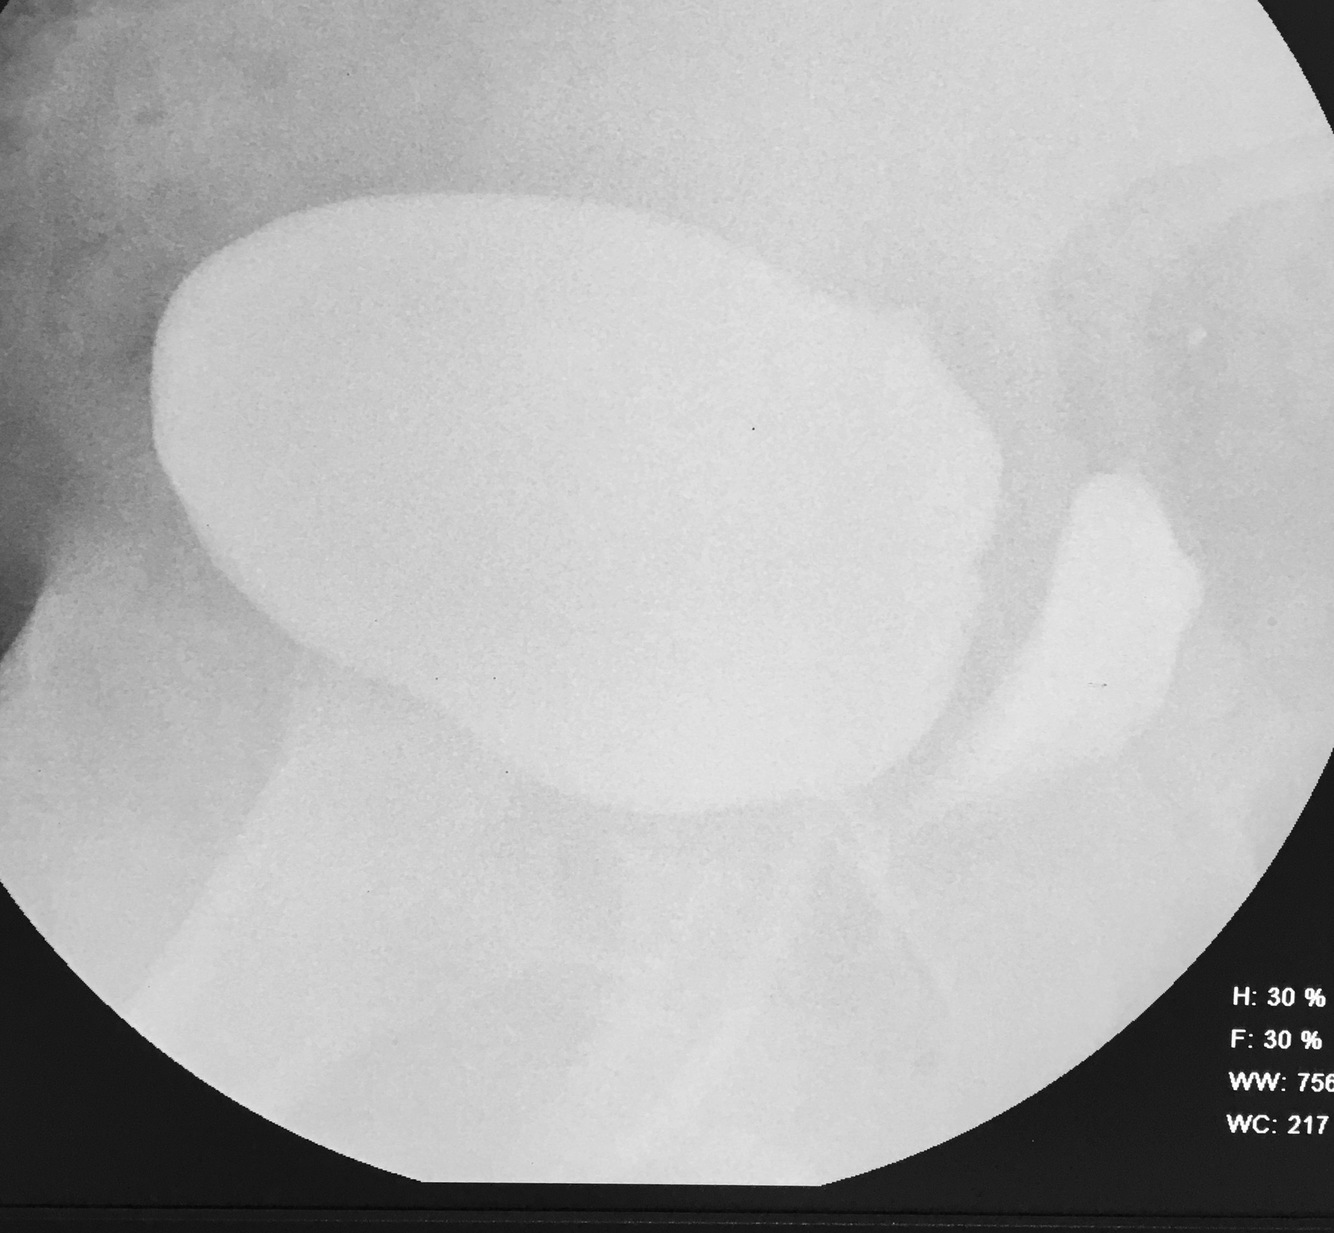

Lymphocele with pressure effect on Tx Kidney

What are 4 causes of this condition?